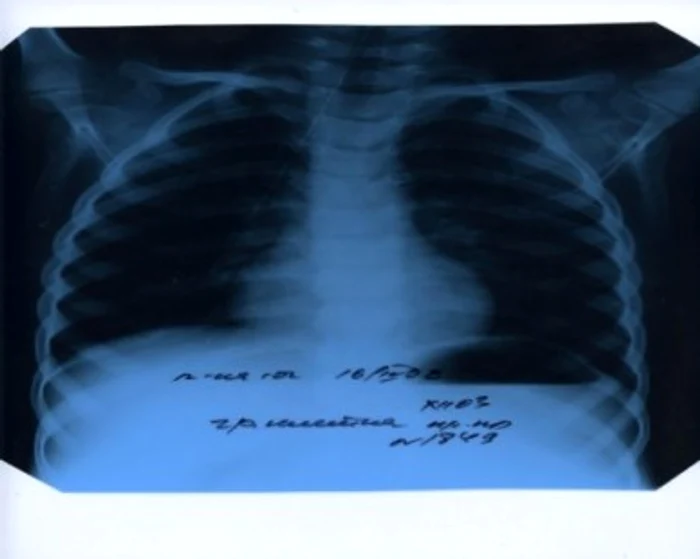

Tuberculoza ar putea fi depistată în doar 100 de minute

Testele microscopice folosite în prezent pentru stabilirea diagnosticului necesitau un interval de aproximativ trei luni. De asemenea, testul poate indica dacă bacilul care a provocat boala este rezistent la medicamentele folosite în tratarea tuberculozei.

Cu ajutorul acestui test se pot diagnostica şi cazurile de tuberculoză combinate cu HIV. Anual, la nivel mondial 1,7 milioane de persoane mor din cauza tuberculozei.